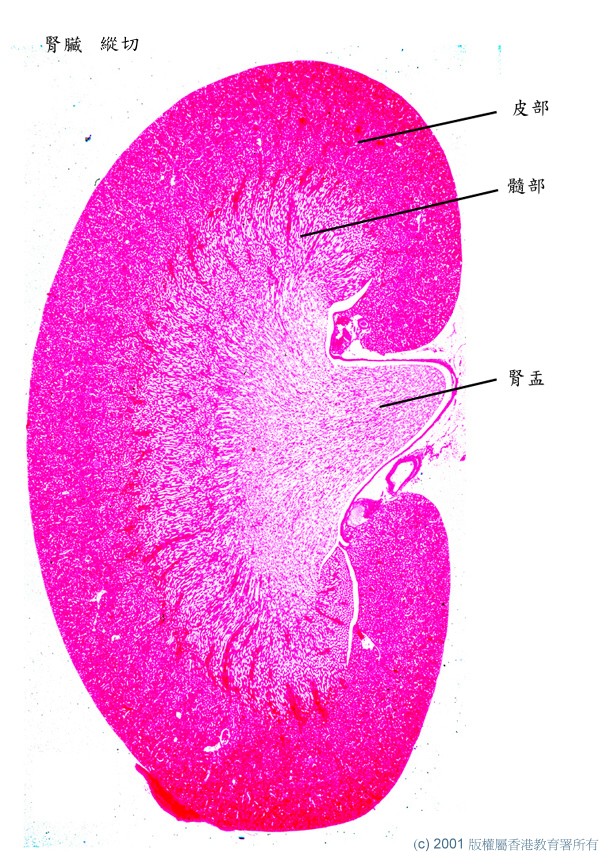

11_腎_ls_labels.jpg